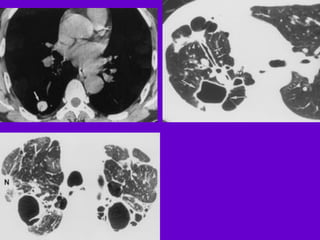

Miliary TB

􀂄 Earliest form of miliary TB is detectable

on HRCT.

􀂄 Coalescing nodules result into patchy

irregular

opacities and HRCT shows this variation

effectively

and has been described as “snowstorm

appearance”.

􀂄 HRCT shows cavitation, which is not

evident on plain

CXR.

Miliary Tuberculosis

Produced by acute dissemination of tubercle

bacilli via the blood stream.The term miliary

derives from the radiological picture of

diffuse, discrete nodular shadows about the

size of millet seed (2mm).